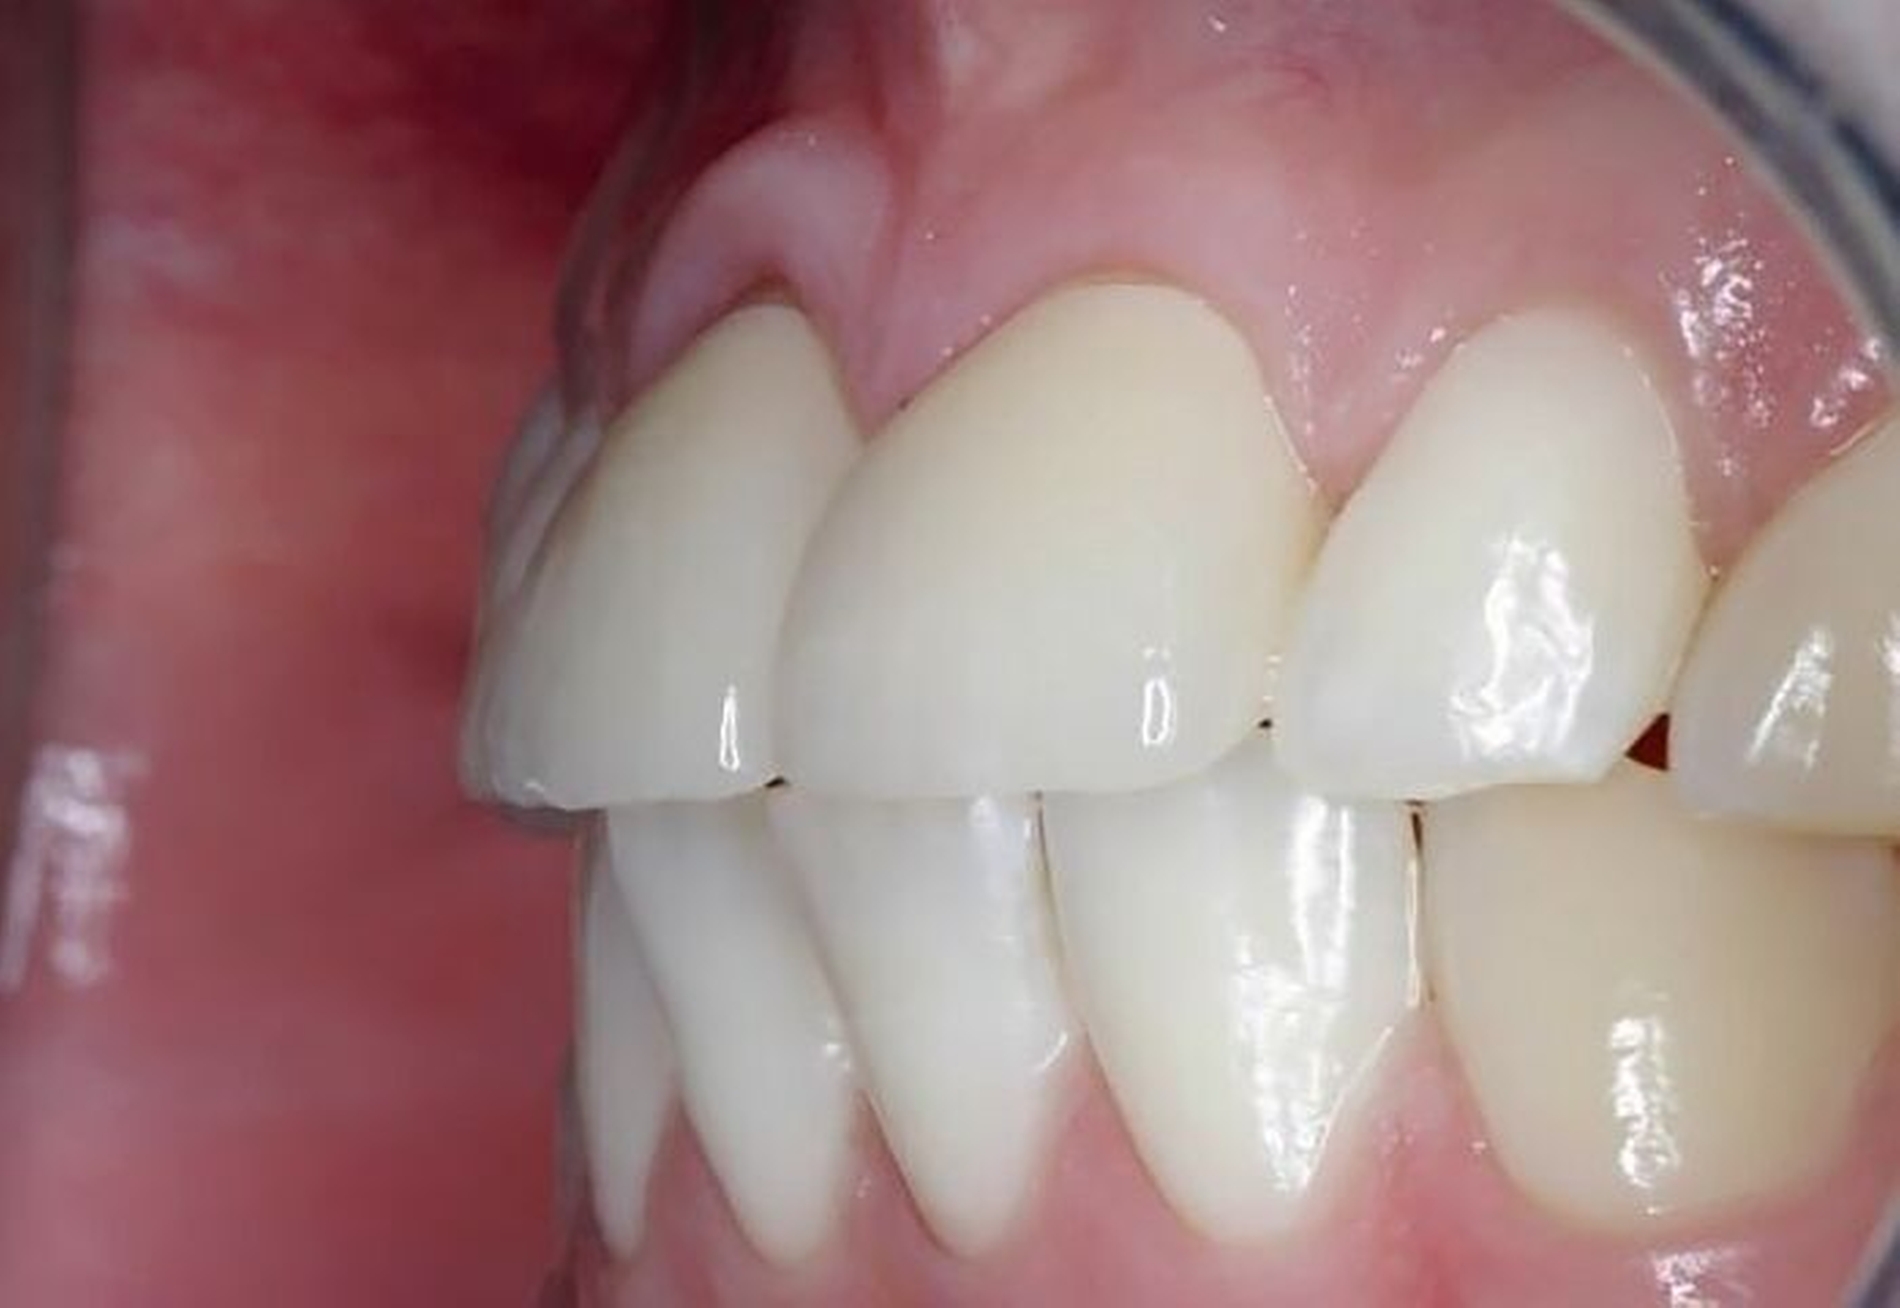

Die Zähne 11 und 21 wurden nach Abschluss der kieferorthopädischen Behandlung mit Lithiumdisilikat-Keramikkronen versorgt (Abbildungen 14 bis 16). Durch die Extrusion waren das Fassen der Frakturkante und die Etablierung des Ferrule-Effekts nun ohne Probleme möglich. Die Eingliederung der Arbeit konnte unter absoluter Trockenlegung erfolgen. Die nach dem Einsetzen angefertigte Einzelzahnaufnahme zeigt die präzise Adaptation der Kronen sowie Umbauprozesse des Alveolarkamms. Drei Jahre nach Therapieabschluss zeigt sich eine suffiziente klinische Situation (Abbildung 17).